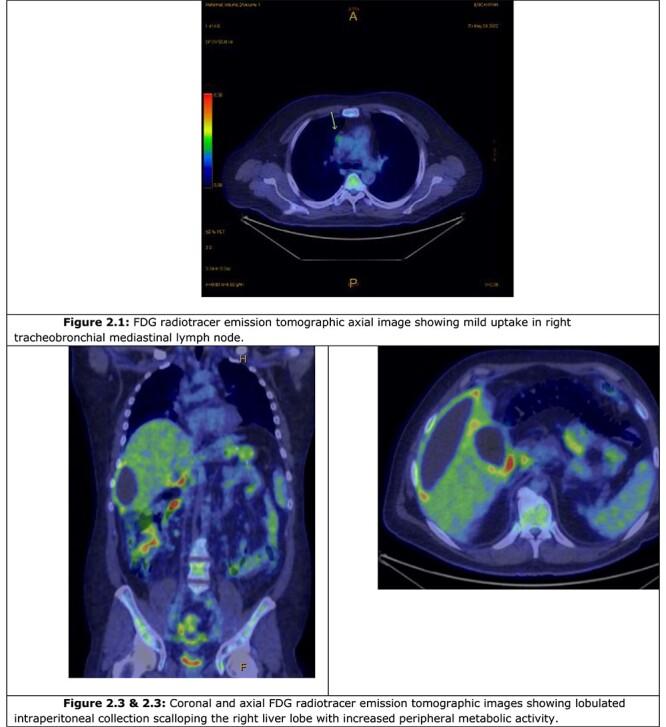

我们报告了一例39岁男性,其出现急性呕吐和腹泻症状。最初按肠胃炎进行经验性治疗,后来影像学检查证实为胆囊炎并发瘘管形成和腹腔内囊肿。胆囊切除术后,组织学检查确诊为黄色肉芽肿性胆囊炎(XGC)。本文详细总结了该病症,并对2017年以来所有XGC病例进行了文献综述,旨在突出有关该疾病性质及其临床表现的诊断结论。